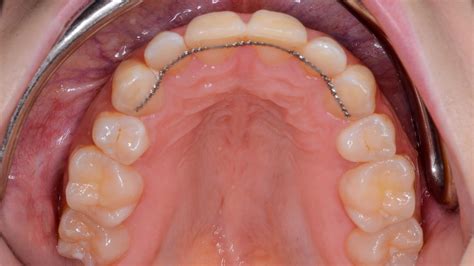

Un retenedor fijo (también llamado retenedor permanente) es un pequeño dispositivo que colocamos al finalizar la ortodoncia para mantener tus dientes en su nueva posición. Consiste en un alambre metálico muy delgado hecho a medida, que va pegado con un adhesivo especial en la parte posterior de ciertos dientes (generalmente los incisivos y caninos inferiores, de colmillo a colmillo). Al ir por detrás de los dientes, no se ve al sonreír y resulta discreto. Una vez colocado, no puede ser retirado por el paciente, sino solo por el ortodoncista si fuera necesario.

El retenedor fijo (barra pegada a la cara interna del diente) es considerado como la mejor opción para evitar movimientos de los dientes, generalmente se colocan detrás de los 4 dientes en la parte superior y detrás los 6 dientes en la parte inferior. Dentro de sus ventajas sobresale por su estética, ya que puedes hablar o sonreír sin que se noten.

Son retenedores que se adhieren a la parte posterior de los dientes anteriores. Su función, al igual que la de los otros tipos, es evitar que los dientes se muevan de su posición final.

Se usan cuando se planea una retención prolongada o si se teme que se pierda, por inestabilidad, el alineamiento obtenido.